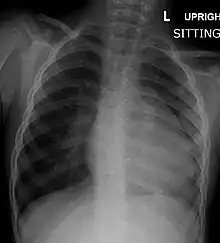

A CXR (Chest X-Ray) of a child with tetralogy of Fallot

Congenital heart defects are now diagnosed with echocardiography, which is quick, involves no radiation, is very specific, and can be done prenatally.[36]

Before more sophisticated techniques became available, chest x-ray was the definitive method of diagnosis. The abnormal "coeur-en-sabot" (boot-like) appearance of a heart with tetralogy of Fallot is classically visible via chest x-ray, although most infants with tetralogy may not show this finding.[37] The boot like shape is due to the right ventricular hypertrophy present in TOF. Lung fields are often dark (absence of interstitial lung markings) due to decreased pulmonary blood flow.[15]:171–72